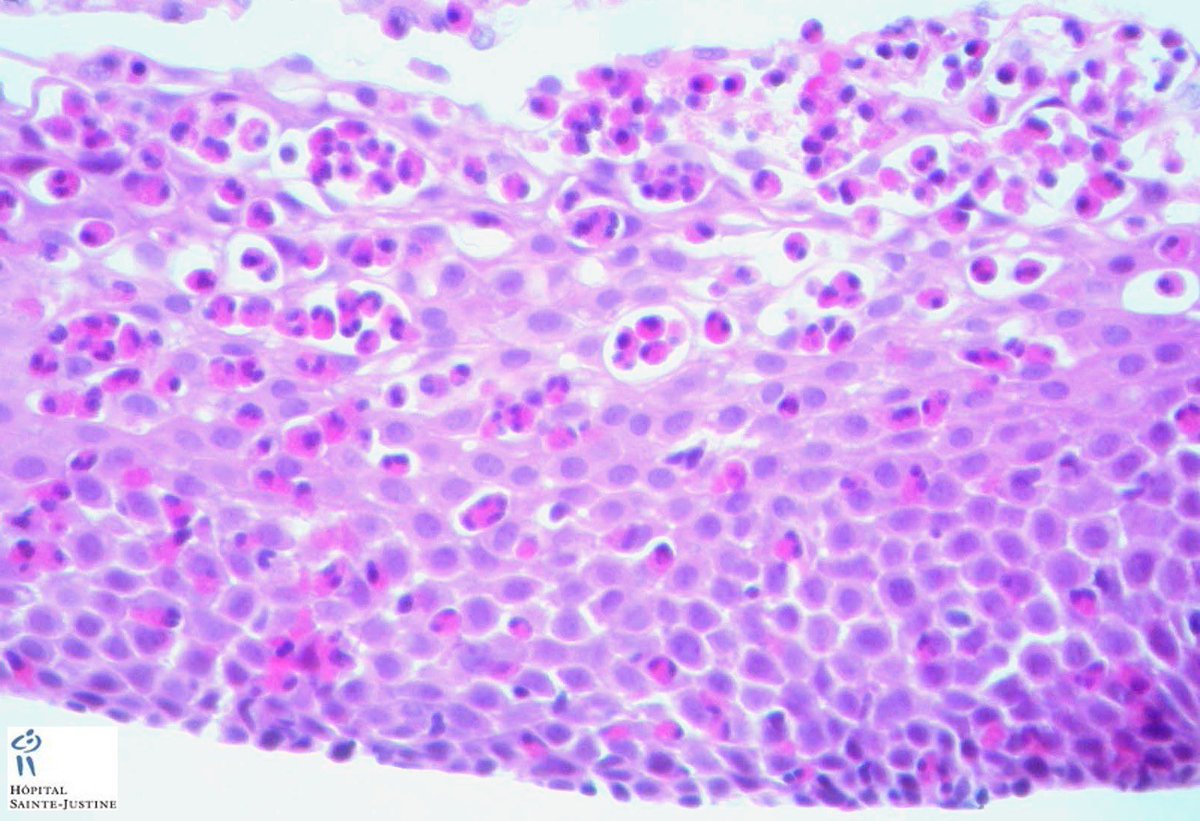

يهمنا من خلايا الجهاز المناعي نوع معين و المعروف ب #Eosinophils و المحتوية على حويصلات ذات تركيز عالي من elastase, peroxide, و غيرها لديها القدرة على زيادة نسبة الالتهاب في المنطقة المصابة و احداث تأثير مدمر على الجراثيم و الانسجة المحيطة بها على حد سواء.

يتم تشخيص الحالة بواسطة منظار المريء الذي عادة ما يظهر تغير في جداره متمثل في وجود حلقات و شقوق في الطبقة السطحية مع ضيق في قطره كما هو موضح في الصورة. تأخذ عينات من جدار المريء و التي عادة ما تظهر زيادة ملحوظة في عدد خلايا #eosinophils